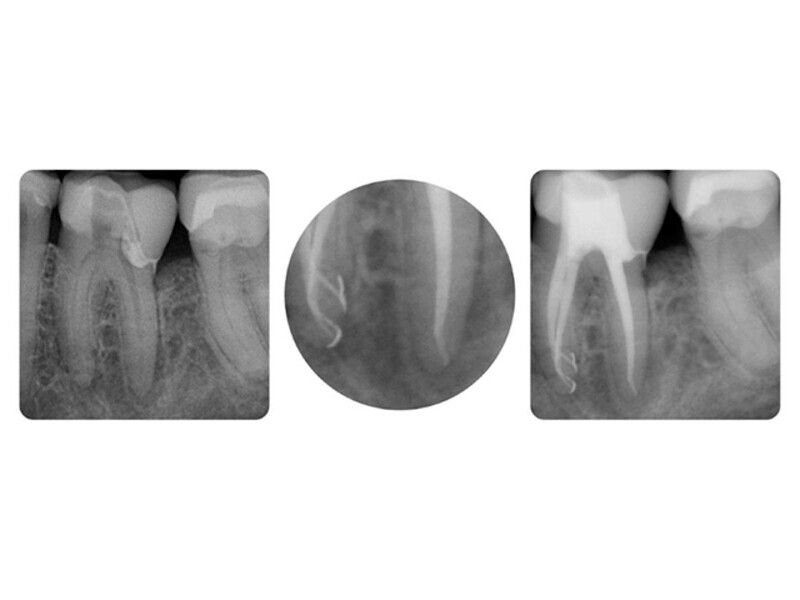

Endodontický výplachový protokol: Koncentrace musí souhlasit